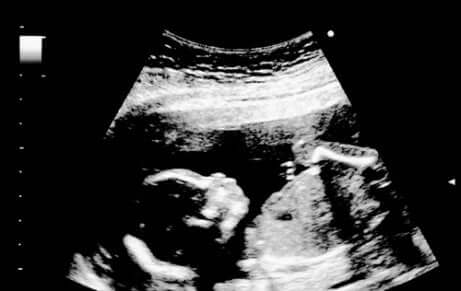

Sikiön liikkeet lisääntyvät ja voimistuvat koko ajan. Ultraäänitutkimuksessa sikiön voidaan nähdä venyttelevän, suoristavan ja koukistavan käsiään ja jalkojaan ja imevän sormiaan. Samassa tutkimuksessa on nähtävissä myös suun avautuminen ja sulkeutuminen, kun sikiö opettelee nielemään. 15 viikon ikäinen sikiö myös ilmeilee ja haukottelee ja toisinaan myös nikottelee, minkä äitikin voi tuntea.